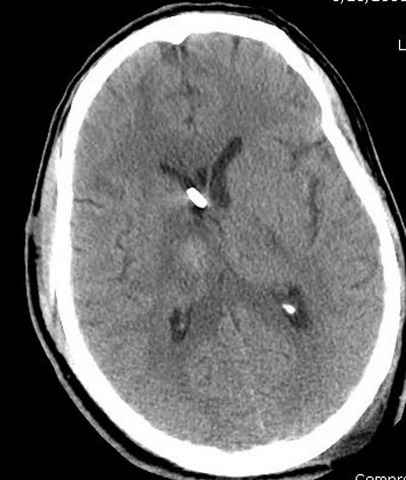

больному 42, автоавария, политравма, открытая черепномозговая травма, безсознании, открытый перелом бедра, размозжение мягких тканей, дефект кожи на передней поверхности бедра около 13 см2 от ожога, компартмент синдром.

Наблюдается службой травмы и нейрохирургии (ICP) Increased Intracranial Pressure by ventricular cateter

больной без сознания, со слов нейрохирурга, наблюдается положительная динамика в нейрохирургическом статусе.

-Согласен, рана до прихода пластического хирурга была 38х13 см, можно было постараться закрыть сверху, а в нижнем отделе где был ожог, применить кожную пластику меньшим размером. К моему удивлению и разочарованию, когда вернулся из другой операционной (шли пареллельные операции), он уже успешно заканчивал свое дело. Кстати недавно разговаривал с нейрохирургом, он снял ICP (intracranial prеssure monitor), внутричерепное давление стабилизировалось, ортопеды и хирурги закончили с лечением, теперь длительное неврологическое восстановление.